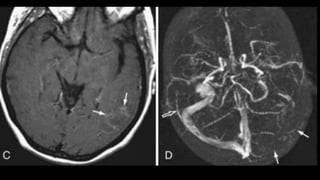

FLAIR- DWI MISMATCH

viable

• #141 These IS THE axial T2shows absence of normal flow void and hyperintense thrombus in SSS and TOF3d multislab image shows filling defect in SSS

• #142 On post contrast axial image, there is filling defect in the left transverse sinus as well …and in SSS as visible in this coronal secttion

• #144 In cases of DST ,IT IS THE dst THAT extends